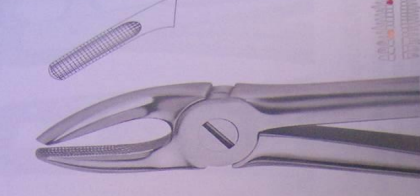

Instrumentation : le Davier

Description

Un davier est formé de trois parties :

- Mors : Partie travaillante, permettant de saisir la dent grâce à leur forme adaptée à la morphologie dentaire.

- Branches : Généralement symétriques, légèrement courbées.

- Charnière : Point d’union des deux bras de l’instrument.

Variétés

Au maxillaire supérieur

Les mors sont dans le prolongement du manche.

- Daviers pour incisives et canines :

- Forme générale rectiligne.

- Daviers pour prémolaires :

- Mors identiques.

- Forme générale en S italique.

- Branches incurvées.